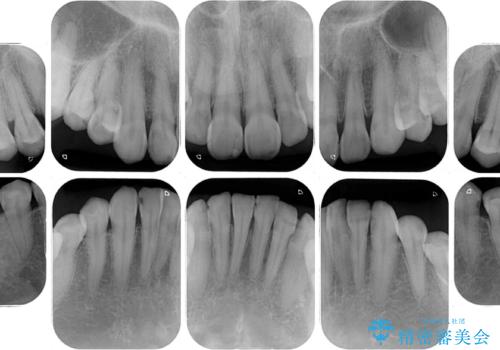

全顎的にむし歯が多く、根管治療の必要奥歯や、審美的に気になっている前歯を中心にオールセラミッククラウンにて補綴治療を行うこととしました。

上顎前歯は歯肉退縮により歯根が露出していたため、事前に歯肉移植術により根面被覆を行い、その後にオールセラミッククラウンを装着することとしました。

- 治療費の目安: 205万円(税込)費用は治療当時の料金となります